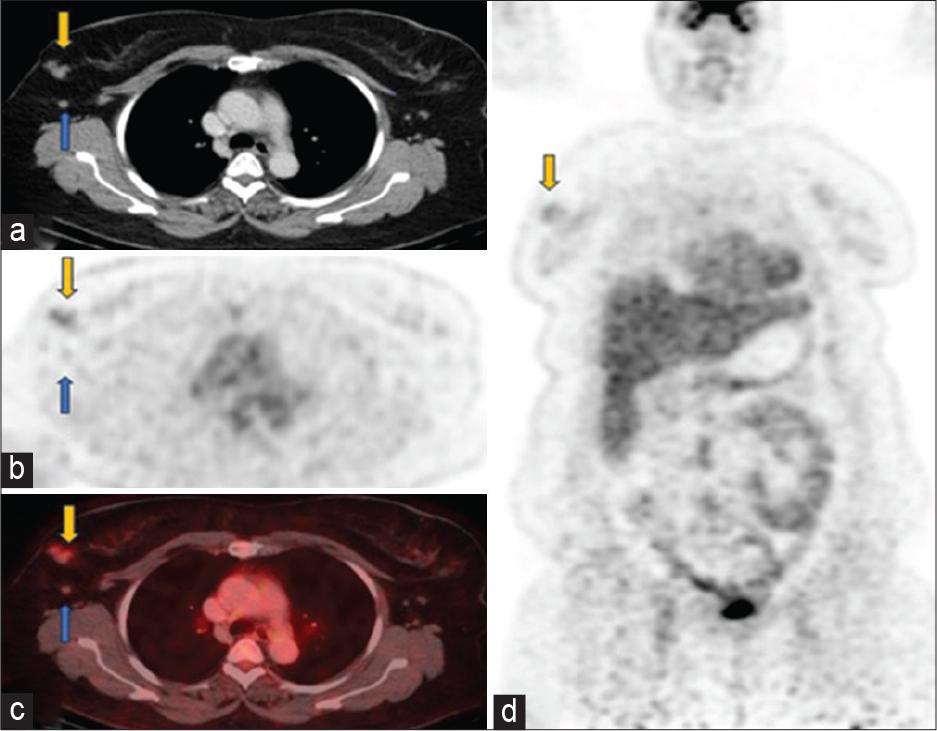

Figure 2: